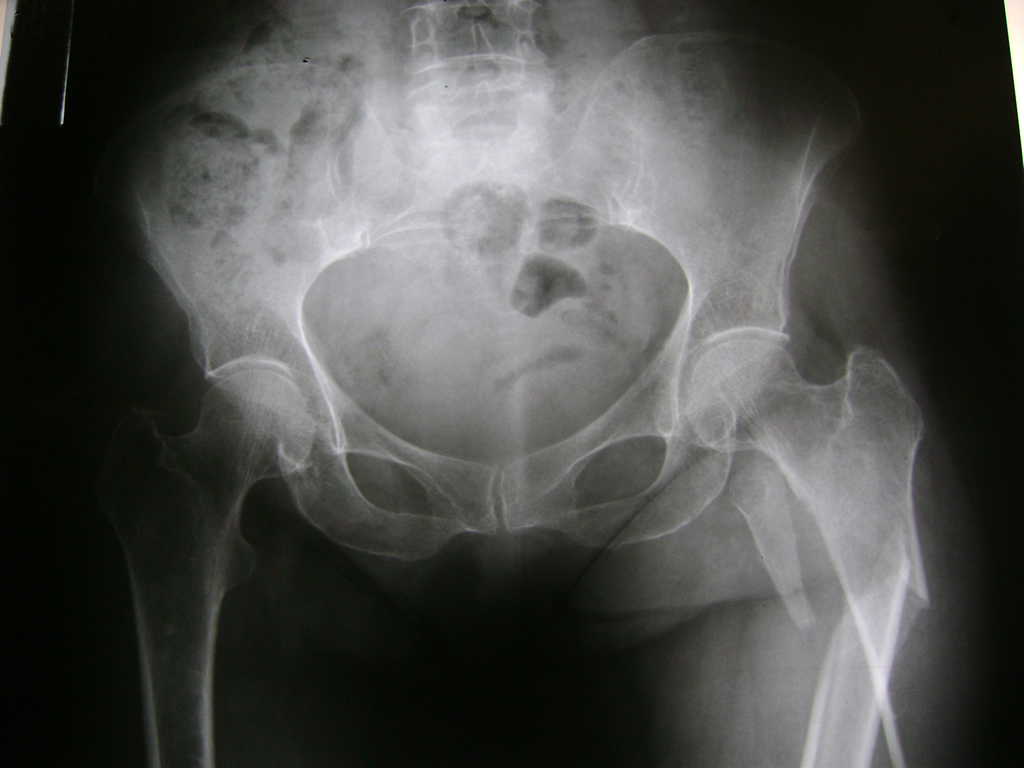

La cirugía de fractura de cadera se realiza para reparar una ruptura en la parte superior del hueso del muslo. Este hueso se denomina fémur.

Es parte de la articulación coxofemoral. Si una fractura de cadera no recibe tratamiento, es posible que deba permanecer en una silla o en la cama.

Esto puede llevar a otros problemas de salud potencialmente mortales, sobre todo si usted es una persona mayor.

A menudo se recomienda la cirugía para reparar la fractura debido a dichos riesgos.